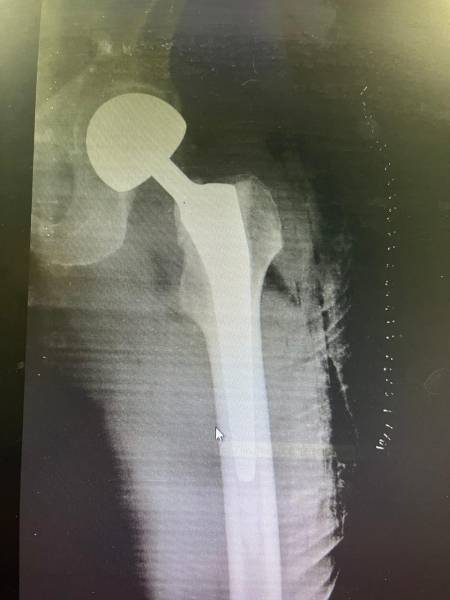

- إجراء عمليات جراحية معقدة و دقيقة في مجال العظام و المفاصل و الكسور و الإصابات ، رغم الضغط الكبير على المستشفى و أعداد المراجعين الكبيرة.

- تطبيق تقنيات جراحية حديثة و متقدمة، و ذلك في ظل التحديات التي يواجهها الفريق بسبب أعداد المرضى و المراجعين الكبيرة.